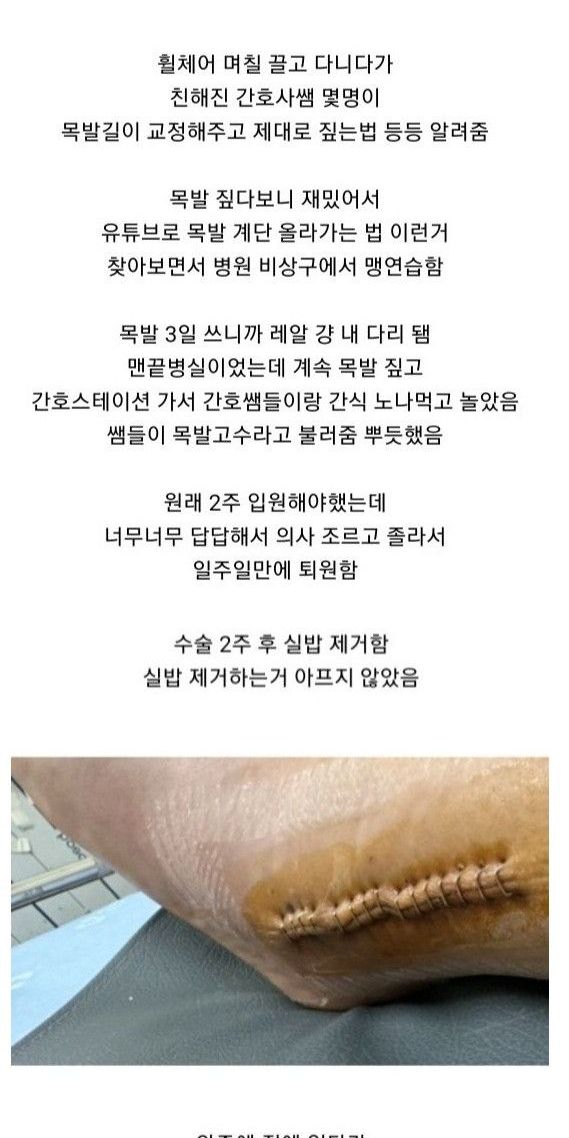

원래는 1년뒤 철심빼기로 했는데 백수되고 한가해서 이참에 하자고 수술날짜 땡겨서 1월초로 수술 잡힘

근데 어차피 시간 남아돌아서 지금하는게 나을거같길래 또 땡겨서 12월에 수술

다음날 걸어다니는거 보고 의사 또 화들짝 바로 퇴원함